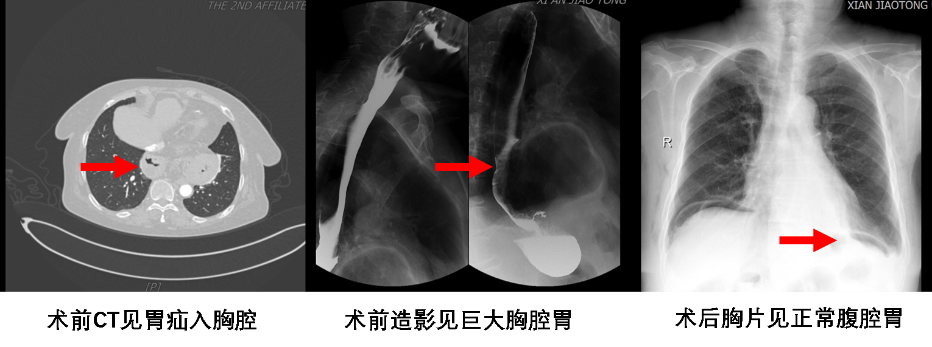

近日,一位年近8旬的老太太来到胸外科就诊,自述因反流严重,多年不能平躺入睡。如果平躺入睡,不到2小时就会因为反酸、烧心而醒来,严重影响休息。长年口服药物,症状反复。姜建涛主任详细查体了解病史后首先考虑到胃食管反流综合征,进一步通过消化道造影、胃镜等检查证实合并食管裂孔疝。该患者属于Ⅲ型食管裂孔疝,且疝囊较大,症状反复,保守治疗无效,手术指征明确。

经过我院姜建涛主任团队详细的术前评估,成功为该高龄患者行腔镜下食管裂孔疝补片修补术及胃底折叠术。手术过程中,发现患者的疝囊异常巨大,长径约10cm,且有接近一半的胃以及胃食管联合部疝入胸腔。面对如此复杂的局面,依然选择了更微创、更精细的腔镜手术。手术成功完成了疝内容物的复位、疝孔补片修补以及360°的胃底折叠术。

术后第1天复查胸片胸腔胃成功复位至腹腔,术后第3天顺利出院,患者自觉反酸症状完全消失,停药后未见症状反复发作。患者非常激动的说“熬了这么多年,终于可以平躺着睡觉了。